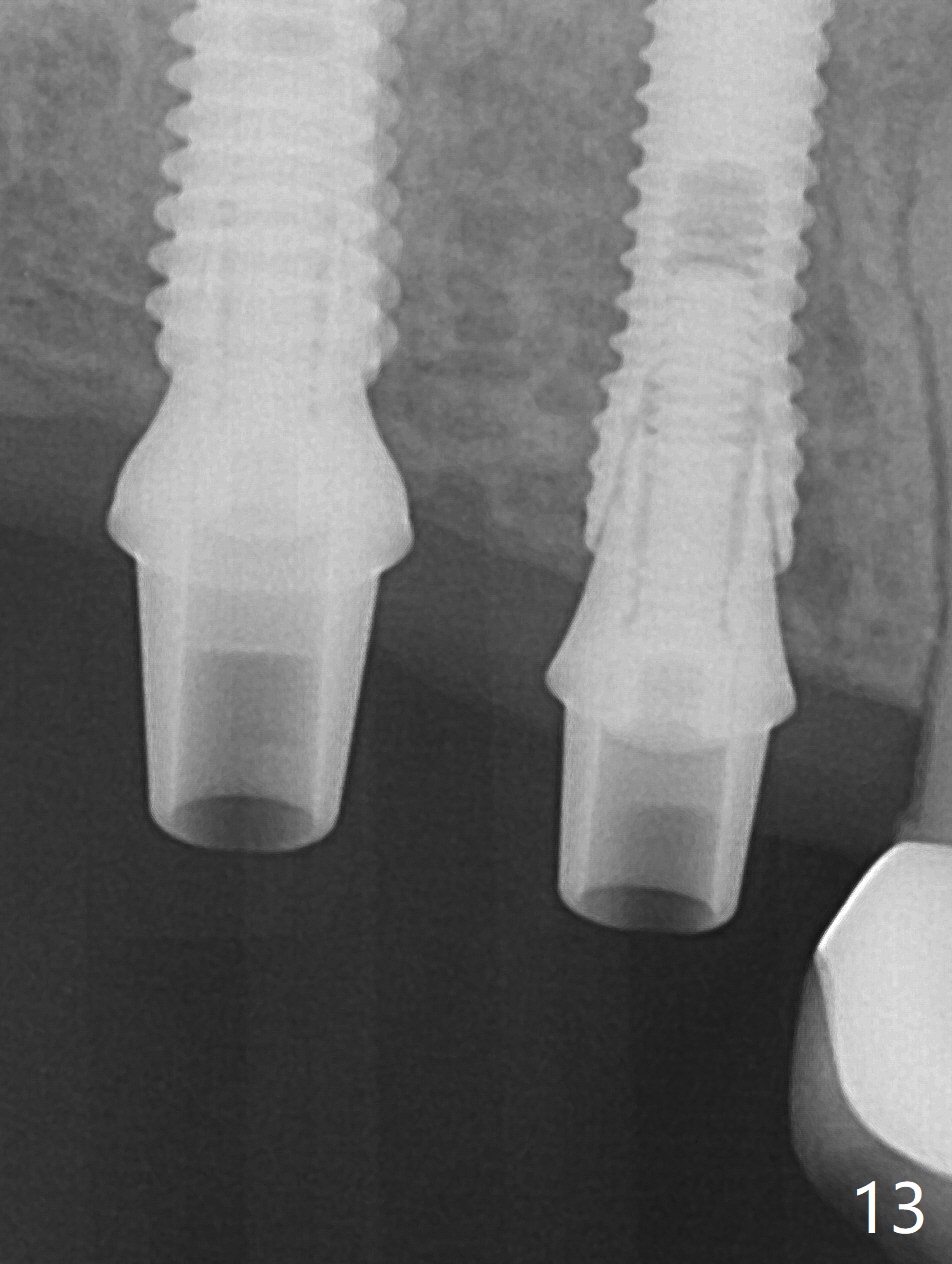

The ridge at #3,4 is wide (Fig.1). A surgical stent is placed (Fig.2) for initial osteotomy (Fig.3). When the stent is removed, the osteotomies need to move palatal (Fig.4 arrows). As two of 1.2 mm drills are in place (Fig.5), mesiodistal trajectories are found off (Fig.6). After the trajectories are corrected (Fig.7), the depth cannot be determined with PA (Fig.8, as compared to Pan (Fig.9)). Following 4.3 and 3.2 mm final drills at #3 and 4, 4.5x13 and 3.8x15 mm implants are placed with insertion torque of 35 and 50 Ncm, followed by 5.5x4(3) and 4.5x4(2) mm abutments (Fig.10). BWs show incomplete placement of the implant at #4 distal (Fig.11,12). Later the implant is placed ~ .5 mm deeper. Periodontal dressing is applied postop. CT-assisted surgical guide must be more efficient for this case with wide ridge. There is no bone loss around the implants 3 moths postop

(Fig.13).